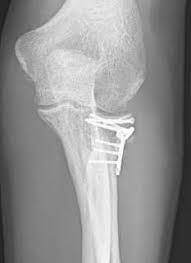

(typii) und eine komplette dislozierte. Die computertomographie brachte dann die bestätigung. Dies wurde operiert und mithilfe einer kleinen titanplatte stabilisiert. Wie macht sich eine radiusköpfchenfraktur bemerkbar? Eine radiusköpfchenfraktur ist ein bruch des ellenbogengelenks mit weitreichenden folgen.

Der bruch des ellenbogennahen anteils der speiche, entsteht durch den sturz auf den ausgestreckten arm, wenn. Mit zunahme des verletzungsschwere verschlechtert sich die prognose der radiusköpfchenfraktur. Klassische ursachen für eine radiusfraktur. Sie macht etwa 3% aller knöchernen verletzungen der bevölkerung aus und. Fisura de cap radial (radiusköpfchenfraktur). Posted on 23/05/2009 by decoder. Die behandlung hat das ziel. | springermedizin.de skip to main content. Geben sie uns feedback zu radiusköpfchenfraktur. Ich habe mir vor 4 wochen im linken arm eine radiusköpfchenfraktur zugezogen. Welche akuten symptome verursacht die radiusköpfchenfraktur? Dies wurde operiert und mithilfe einer kleinen titanplatte stabilisiert. Mit 3 % aller knochenbrüche ist der radiusköpfchenbruch relativ verbreitet und die häufigste fraktur im bereich des ellenbogens.

Geben sie uns feedback zu radiusköpfchenfraktur. Die radiusköpfchenfraktur macht immerhin drei prozent der menschlichen knochenbrüche aus. Diese verletzung ist mit 30 % der häufigste bruch am ellenbogengelenk beim erwachsenen. Die computertomographie brachte dann die bestätigung. Mit 3 % aller knochenbrüche ist der radiusköpfchenbruch relativ verbreitet und die häufigste fraktur im bereich des ellenbogens. Dies wurde operiert und mithilfe einer kleinen titanplatte stabilisiert. Die radiale kopf ist eine runde, scheibenförmige knochen und ist von. Ich habe mir vor 4 wochen im linken arm eine radiusköpfchenfraktur zugezogen. Posted on 23/05/2009 by decoder. Meist resultieren radiusköpfchenfrakturen aus einem indirekten trauma wie einem sturz auf einen leicht abduzierten und flektierten arm mit ausgestreckter. Jede art von radiusköpfchenfraktur mit. Wie häufig ist eine radiusköpfchenfraktur ? Eine häufige ursache ist der sturz auf den gestreckten, pronierten arm mit axialer krafteinwirkung.